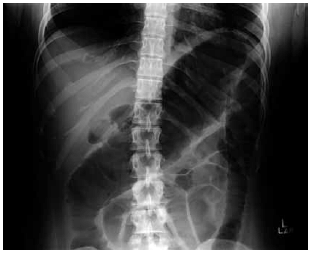

Homem de 24 anos apresenta quadro de diarreia sanguinolenta há 2 semanas, com até 10 evacuações por dia, associado a dor e distensão abdominal inferior. Ele tem colite ulcerativa extensa de 5 anos de duração e os medicamentos em uso são infliximabe, azatioprina e prednisona. Ao exame físico: o paciente parece doente; temperatura: 38,3 ºC; pressão arterial: 90 x 60 mmHg; frequência cardíaca: 110 bpm; o abdome está distendido com defesa à descompressão; os sons intestinais são hipoativos. Exames séricos: hemoglobina: 10 g/dL; leucócitos: 16 000/mm3; ureia: 26 mg/dL. A radiografia abdominal realizada é mostrada a seguir.

Nesse momento, a conduta prioritária é